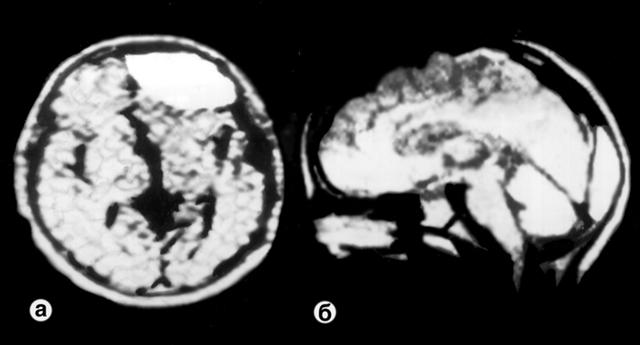

Рис. 3. Магнитно-резонансные томограммы при эпидуральной гематоме: а — в лобной доле (аксиальный срез); б — в области полюса затылочной доли (сагиттальная проекция).